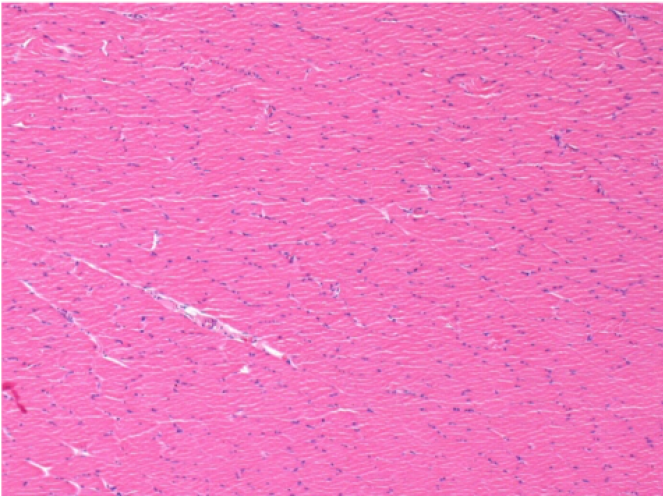

Endopeel Enjeksiyonundan 1 ay sonra sağ pretibial kasta 0.1ml.

Resimlerde siyah olarak görülen şey, bazı bilim adamlarının hayal edebileceği gibi bir nekroz değildir!

Aslında, 4 sonuç dikkate alınmalıdır